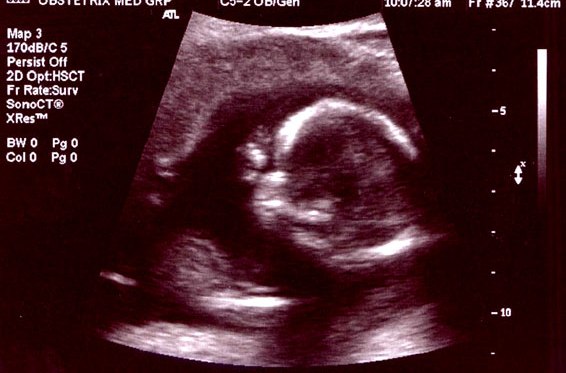

Routine Pregnancy Scan

Ultrasound is a very useful technique during pregnancy to rule out any congenital abnormality in the growing fetus inside the uterus. Not just the health of the baby, but also the health of the to-be-mother can be determined with the help of ultrasounds. It helps in measuring the growth of the baby in terms of her weight and height. Gynecologists recommend regular ultrasounds to check the levels of amniotic fluid, to rule out multiple pregnancies or ectopic pregnancy, to estimate delivery date, and to measure cervical length as well.

Anomaly Scan

Anomaly Scan or mid-pregnancy scan is an ultrasound scan done between the 18th and 21st week of pregnancy to take a closer look at the baby and the womb (uterus) and to have an idea where the placenta is lying. This scan aims to look for any major physical abnormalities in the growing baby. Although it can’t pick up every problem, it gives an idea about the baby’s bones, heart, brain, spinal cord, face, kidneys, and abdomen and allows the identification of the following conditions (some of which are very rare):